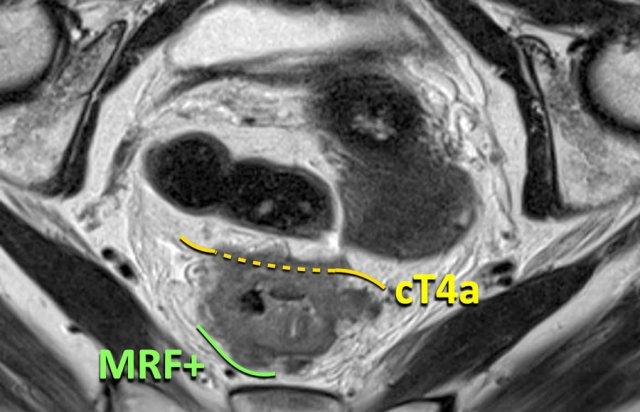

Cạm bẫy: Phân biệt MRF với Xâm lấn Phúc mạc trong Khối u Thành trước

Nguyên tắc chính:

- Ở phía trước, sự xâm lấn MRF chỉ có thể xảy ra trong các khối u nằm dưới nếp phúc mạc, được ghi nhận là T3 MRF+

Các khối u phía trước nằm trên mức phản chiếu phúc mạc mà xâm lấn phúc mạc nên được báo cáo là T4a MRF - Ở phía sau, MRF kéo dài trên mức phản chiếu phúc mạc. Sự xâm lấn đồng thời của MRF (phía sau) và phúc mạc (phía trước) có thể xảy ra, trường hợp này cần được báo cáo là T4a MRF+

Khối u cT4a MRF+

Khối u trực tràng gần này cho thấy sự xâm lấn kết hợp:

- Phía trước: Xâm lấn phúc mạc (T4a)

- Sau: Xâm lấn mạc trực tràng (MRF) (MRF+)